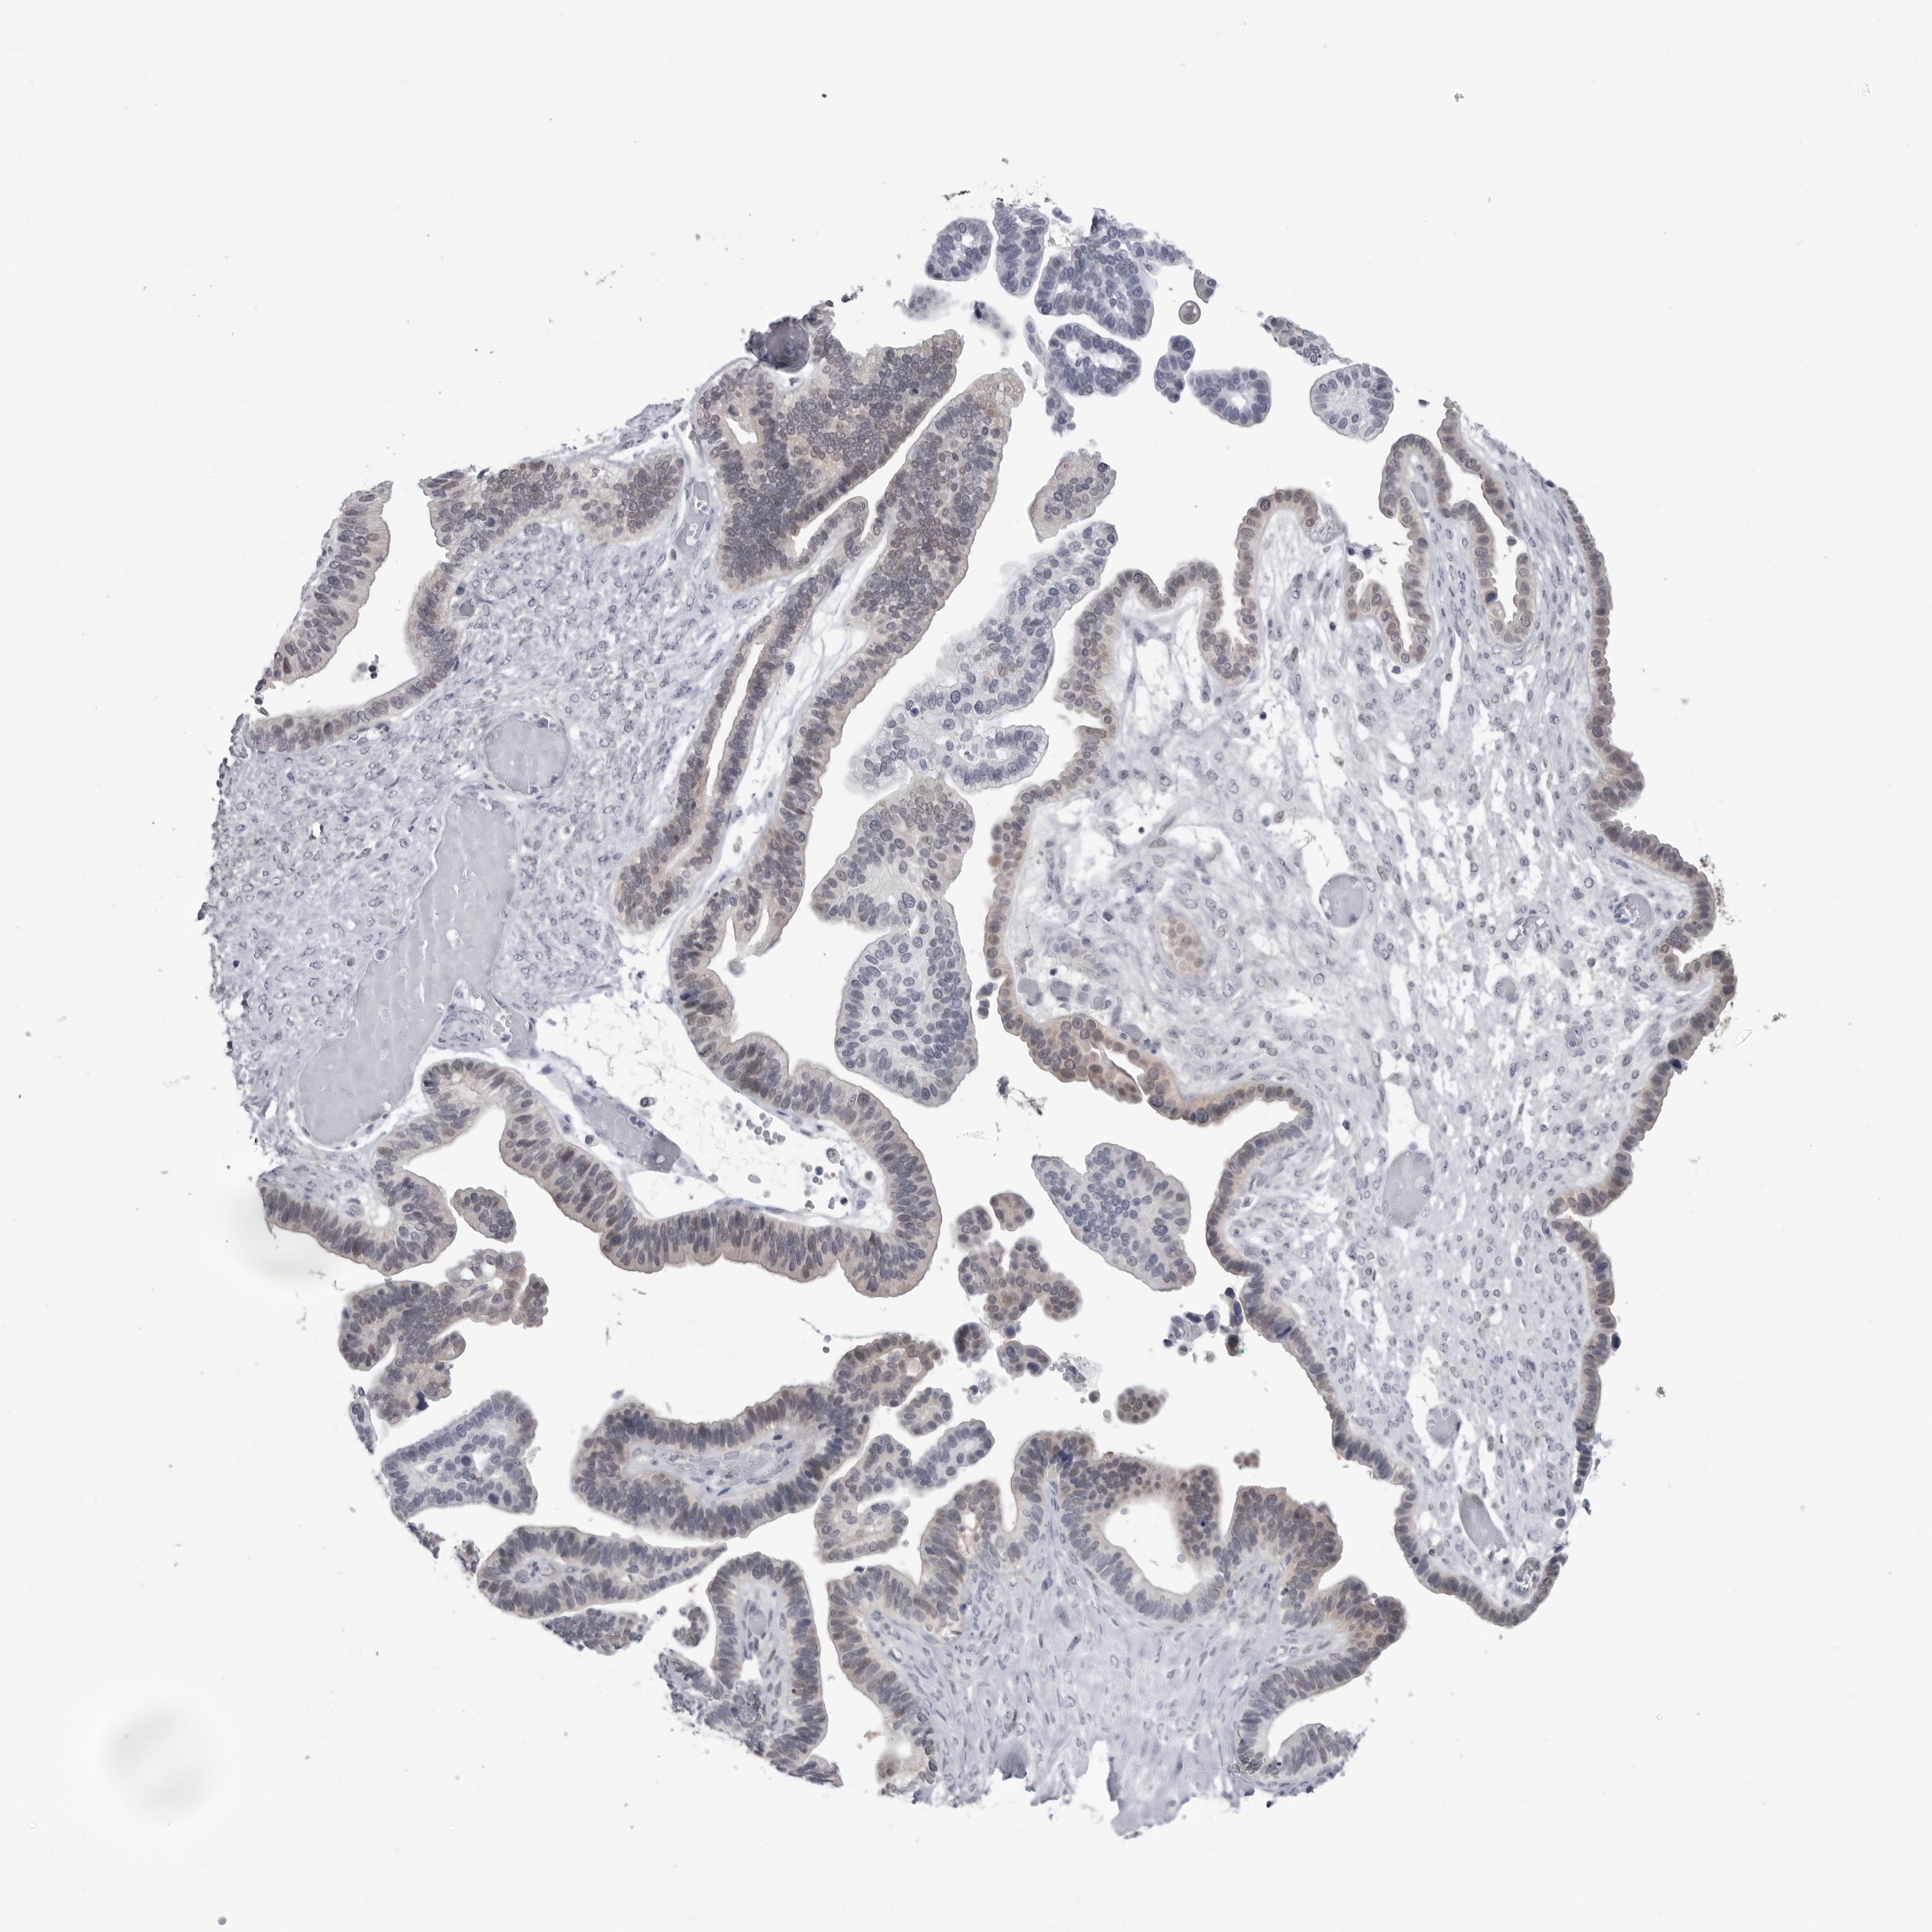

OVARIAN CANCER - Protein expressioni

A mouse-over function shows sample information and annotation data. Click on an image to view it in a full screen mode. Samples can be filtered based on level of antibody staining by selecting one or several of the following categories: high, medium, low and not detected. The assay and annotation is described here.

Note that samples used for immunohistochemistry by the Human Protein Atlas do not correspond to samples in the TCGA dataset.

Antibody stainingi

Antibody staining in the annotated cell types in the current human tissue is reported as not detected, low, medium, or high, based on conventional immunohistochemistry profiling in selected tissues. This score is based on the combination of the staining intensity and fraction of stained cells.

Each image is clickable and will lead to virtual microscopy that enables deeper exploration of all samples and also displays staining intensity scores, fraction scores and subcellular localization as well as patient and tissue information for each sample.

Antibody HPA023204

Antibody HPA027776

Staining

High

Medium

Low

Not detected

Location

Nuclear

Cytoplasmic/membranous

Cytoplasmic/membranous,nuclear

None

Cystadenocarcinoma, serous, NOS

Carcinoma, endometroid

Cystadenocarcinoma, mucinous, NOS

Carcinoma, NOS